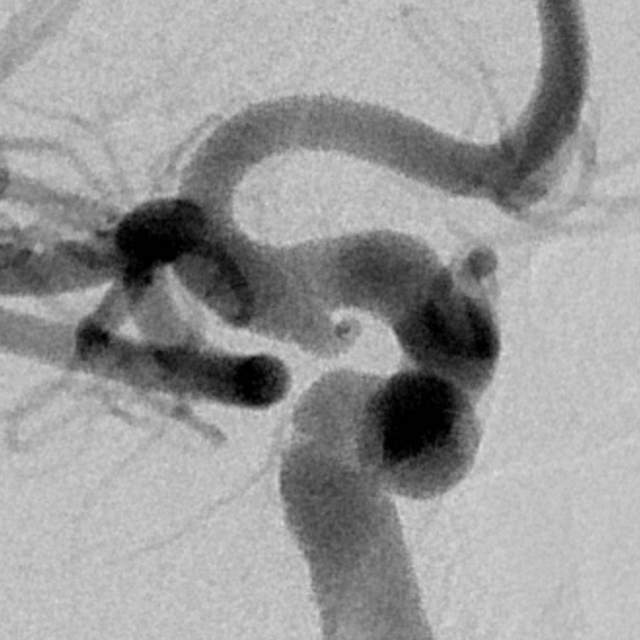

病情变化:中年男性患者,由于头晕查体发现后交通动脉瘤,第一次造影可见形态尚规则,患者及家属经过反反复复的思想斗争,决定采用外科干预。3天后,术中发现动脉瘤的形态已经出现改变,瘤囊的远端出现子瘤。

患者选择:一般而言,这种进展性形态变化伴有子瘤的病变容易出现破裂出血,患者的本次决定真是不失时机的明智之选。

术中评估:动脉瘤位于后交通段的位置,靠近颈内动脉分叉部,颈内动脉交通段的长度相对短小,而且呈现喇叭口的形态,支架不容易锚定,容易出现跳跃“”嗑瓜子”现象。如果支架超过分叉部,覆盖大脑前动脉的起始部,可能会造成后续的大脑前动脉的血管变细。